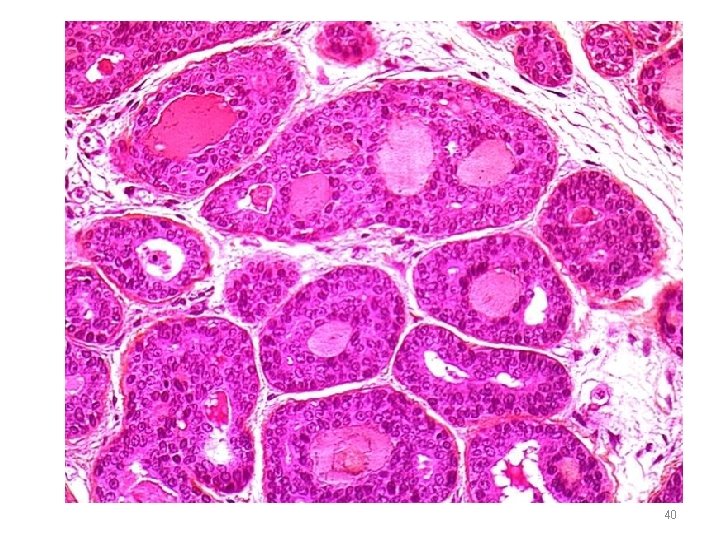

ADENOID CYSTIC CARCINOMA Microscopy • Small cells with dark compact nuclei, scanty cytoplasm • Arranged in tubules, solid, cribriform • SPACES BETWEEN CELLS FILLED WITH HYALINE MATERIAL – basement membrane material • Perineural invasion - pain 38

40